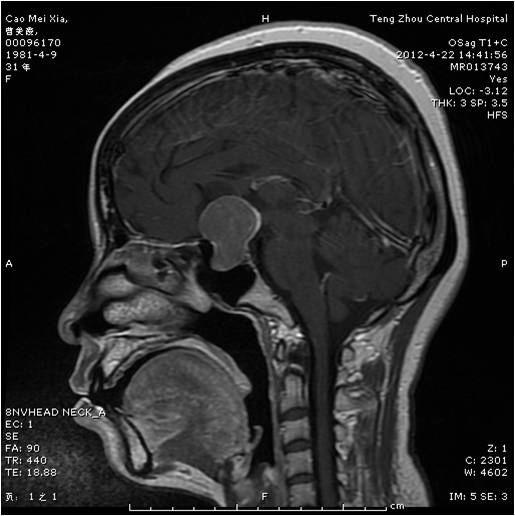

【手術(shù)圖片】

動脈瘤夾閉術(shù)前 動脈瘤夾閉術(shù)后

垂體瘤術(shù)前 垂體瘤術(shù)后